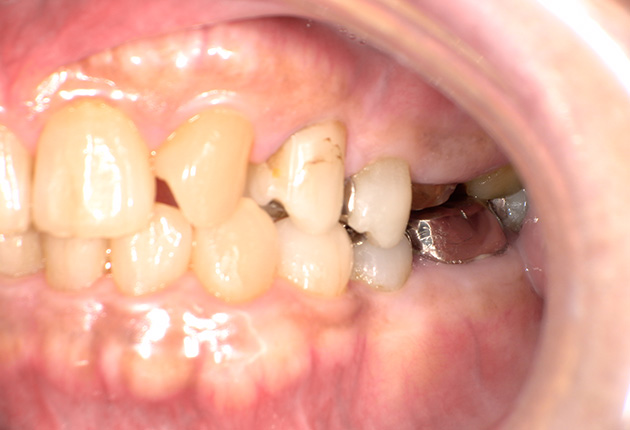

よく噛めず笑うと銀歯が目立つので気にされていました。

| 主訴 | ブリッジ脱離、しっかり噛めない |

| 診査診断 | 上顎歯牙欠損、歯周病、不良補綴、根尖性周囲炎。 不正咬合により噛み合わせのバランスが悪い事が原因により咬合治療が必要。 |

| 治療内容 | 欠損部インプラント 不正咬合に対し不良補綴のやり直しと合わせて咬合再構築 |